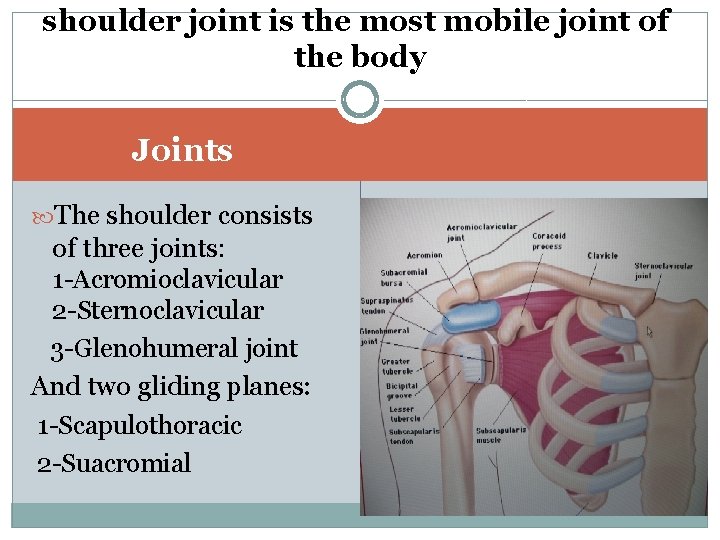

Anatomy of the shoulder

Anatomy of the shoulder

shoulder joint is the most mobile joint of the body Joints The shoulder consists of three joints: 1 -Acromioclavicular 2 -Sternoclavicular 3 -Glenohumeral joint And two gliding planes: 1 -Scapulothoracic 2 -Suacromial